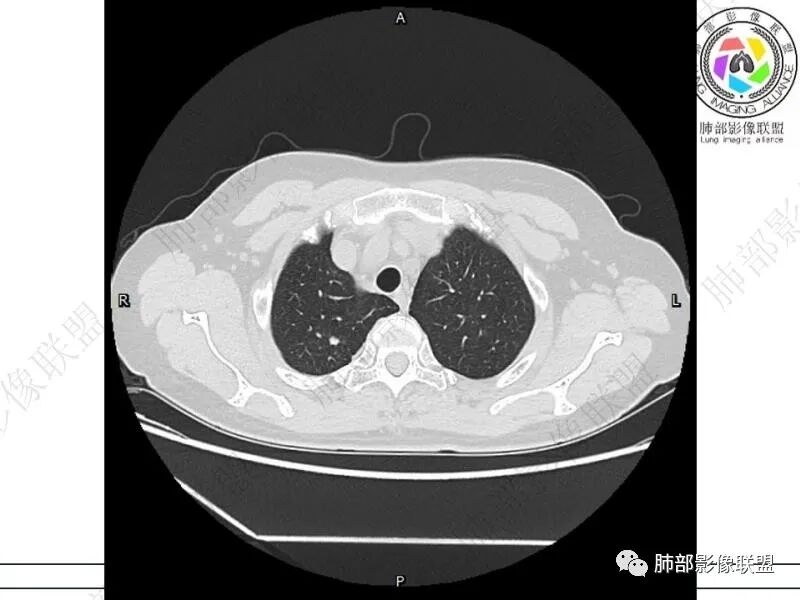

摘星空竹子:两肺胸膜下多发实性结节、磨玻璃影及实变影,短期复查病变有所进展,考虑感染性病变,隐球菌可能,患者有右半结肠癌手术史,转移不能除外。

简单:双肺及胸膜下多发小结节,双下肺胸膜下宽基底团块影,短期内病灶进展考虑炎性病变,隐球?患者ca术后,双肺小结节随诊除外转移

谢加平:结肠癌术后史,两肺胸膜下多发结节及斑块实变病灶,实边边界平直征(亚急性和慢性病变过程),双肺下叶后基底段胸膜下为甚,与胸膜平行特点,见支气管充气征,边缘模糊的GG0,首诊2022年11月18日肺部CT,与治疗11月28日对比,病灶未吸收,双肺下叶胸膜下病灶有侧向融合特点,综合分析符合炎性肉芽肿,隐球菌感染。

冰柠雨露:双肺多发小结节,斑片灶,复查双上小结节有的缩小变性,双下叶病灶增大,内见支气管像,抗感染效果不好,荚膜阴性,支气管灌洗未检出细菌,非感染性病变?淋巴瘤?

老年女性,结肠癌术后。两下肺胸膜下为主片状实变,右下肺短期复查融合且病灶长轴平行于胸膜,实变内可见支气管充气征,边缘磨玻璃晕,另两肺内胸膜下散在数枚小结节状、楔形实性灶。考虑感染性病变,隐球菌可能,鉴别肺转移。

1.老年男性,肠癌术后低热,低免疫状态。C反应蛋白升高,隐球菌荚膜抗原检测阴性。

2.影像特征:双肺胸膜下多发实性结节、磨玻璃影及实变影,胸膜下优势分布、晕征、胸膜下脂肪间隙存在,部分病灶边界平直征,有侧向融合趋势。

3.CEA复查1.8ng/ml,常规情况,基本排除转移。广谱抗生素治疗后无效,病灶仍然进展,考虑特殊感染。